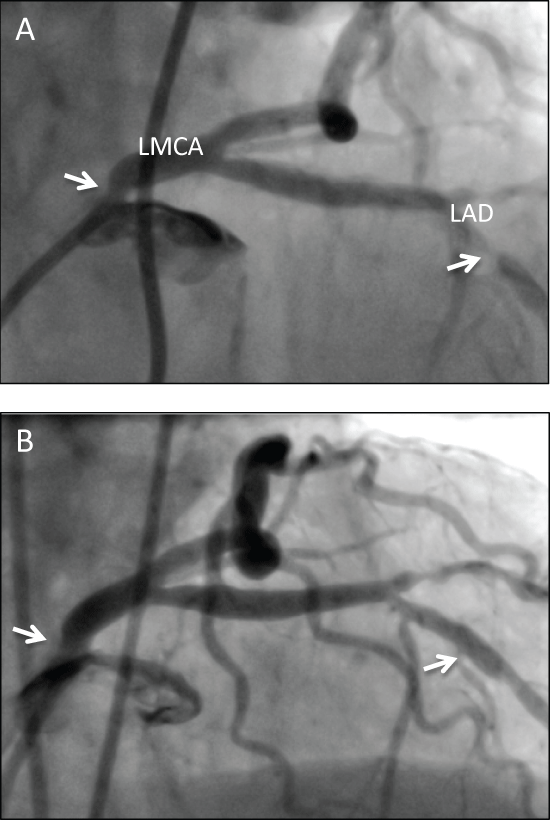

Angiography revealed an ostial left main coronary artery (LMCA) 90% stenosis, mid left anterior descending (LAD) 70% stenosis and a first diagonal 80% stenosis (Figure 1). She was deemed to be unsuitable for coronary artery bypass grafting due to frailty and co morbidities. Haematology consulted suggested if coronary intervention were to be contemplated ideally bare metal stenting (BMS) should be considered to lessen the time on dual antiplatelet therapy, with increased prednisone dose and close monitoring of platelet count. She underwent coronary stenting to both LMCA and LAD stenosis. A 6F XB3.0 guide catheter was used with a 0.014 Run-through Floppy wire (Terumo Corp, Tokyo, Japan, via the femoral approach. A novel drug eluting stent (DES) (Synergy 3.5 × 12 mm, Boston Scientific, Natick, MA, USA) was used for the LMCA, and a BMS (2.75 × 12 mm integrity, Boston Scientific) to the LAD. The diagonal branch was not treated on this occasion given a small myocardial territory subtended. The Synergy stent has a novel design with a bioabsorbable polymer that elutes everolimus placed only on the abluminal stent surface, and is further discussed below. The patient remains well at 3 months post discharge, with a plan to continue aspirin, taper her prednisone, and stop her clopidogrel at 6 months or earlier, if there was any evidence of intolerance or bleeding secondary to the combination, with this duration determined by the Synergy drug eluting stent rather than the bare metal stent.

Figure 1 A) Angiography prior to coronary stenting: RAO 38, Cranial 23 angiography revealing ostial left main coronary artery stenosis (LMCA) (estimated at 90% in RAO 28, caud 19 view not shown) indicated by white arrow, and left anterior descending coronary stenosis (LAD) indicated by white arrow; B) Angiography post coronary stenting: RAO 38, Cranial 23 view. Stents marked by white arrows at prior points of stenosis in LMCA and LAD with excellent angiographic result.